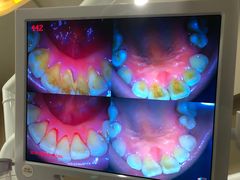

• 土豆口腔(凤凰北总店)

• -土豆口腔(凤凰北总店)